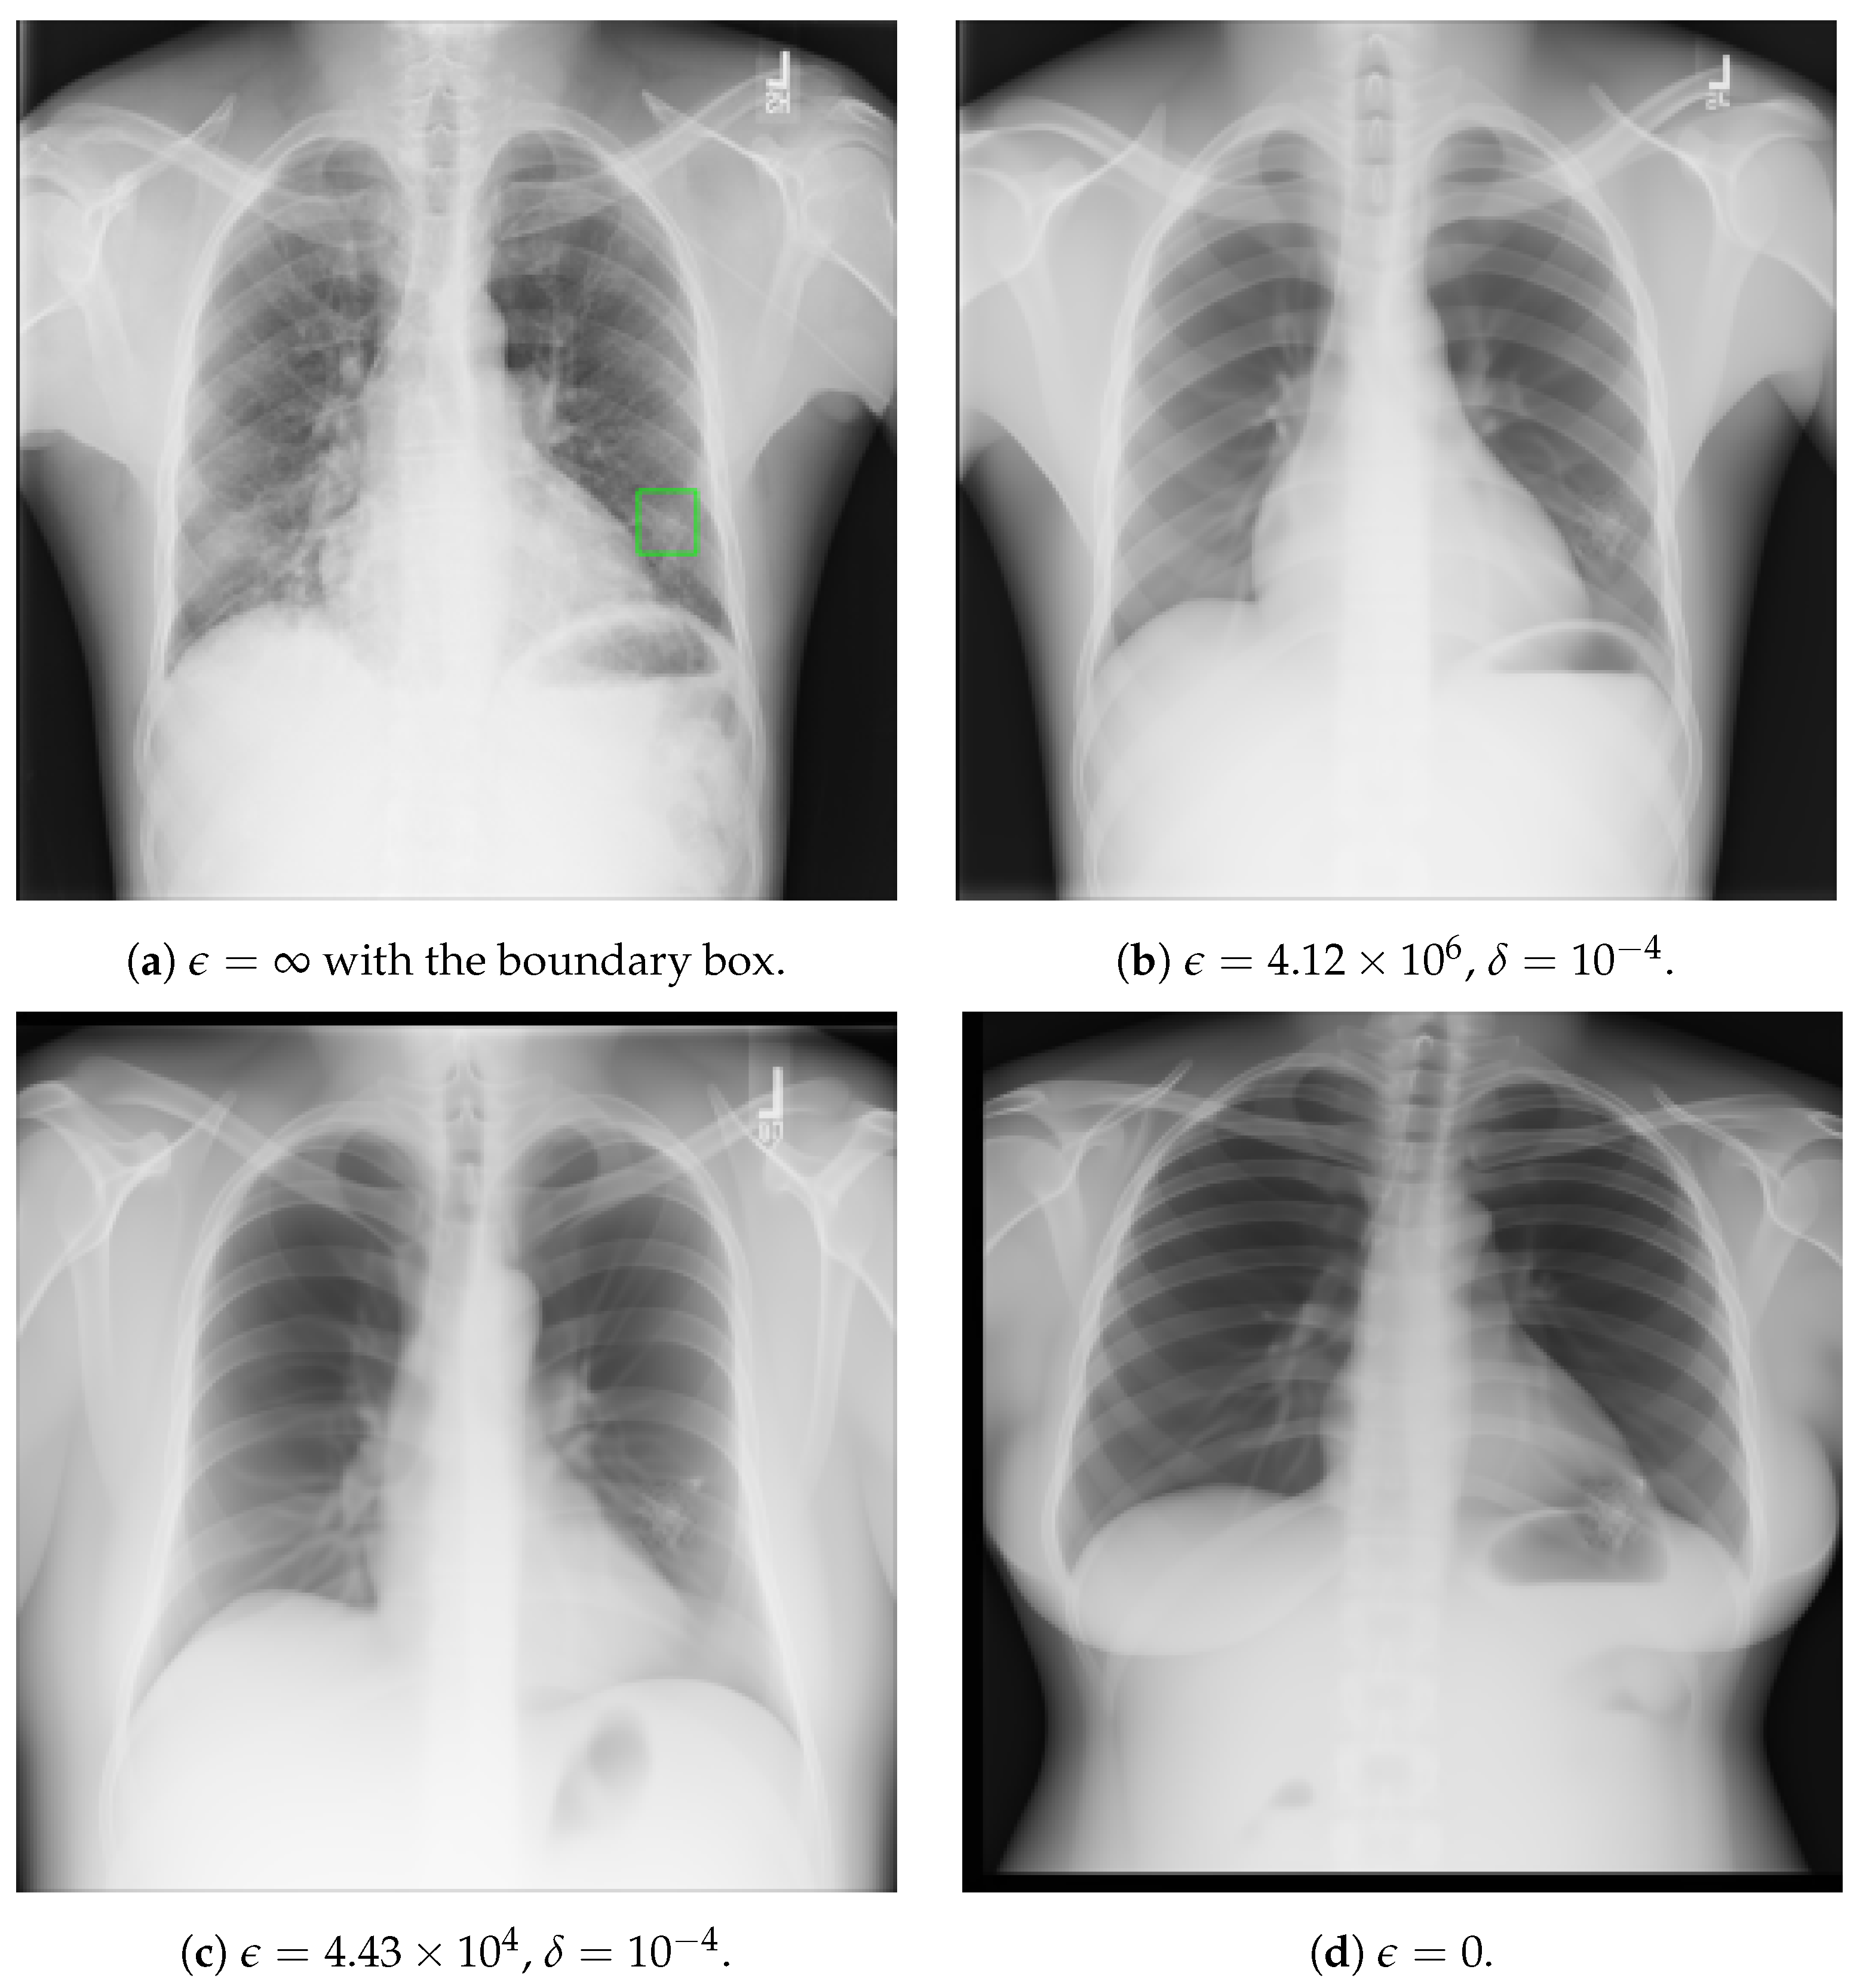

Figure 2 shows the results of CXR image processing using the proposed method. Table 1, Table 2 and Table 3 show the relationship (the raw data) between privacy protection and utility for CXR obtained from this experiment. Utility was evaluated by averaging the results of the first and second evaluation criteria. And the privacy protection metric was directly taken from the results of the third evaluation criterion.

Figure 2. Example of image processing using the proposed method. The “Mass” exists within the green box. Although we illustrate the case of “Mass” here, it was also applied to nine other different types of lesions. It should be noted that the privacy budget here is defined outside the abnormal regions, and within the abnormal regions, the privacy budget is always infinite.

It can be observed that as the privacy budget increases, the strength of privacy protection decreases and utility slightly increases. Even when the privacy budget is at its maximum, the utility does not reach its peak, indicating room for improvement in the extrapolation algorithm. On the other hand, even when the privacy budget is at its minimum ( ϵ = 0 ), the strength of privacy protection does not reach its maximum (P5), revealing that individuals can still be somewhat identified based on the lesions alone.